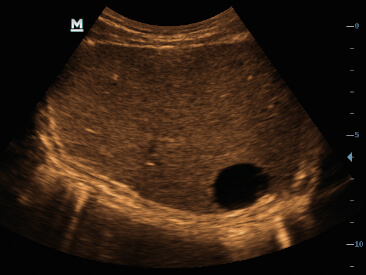

Gambar Klinis